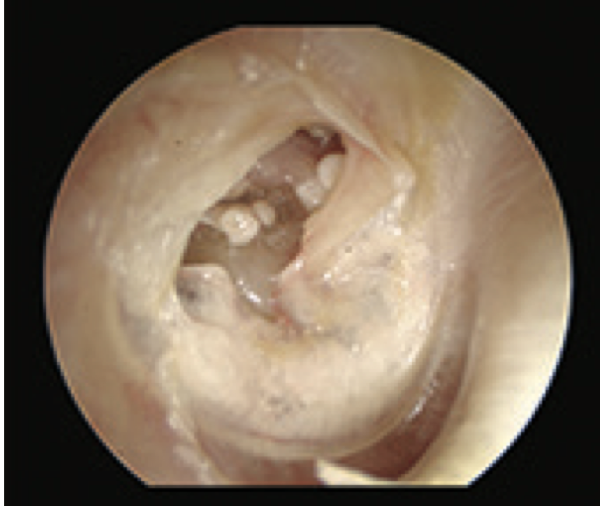

Q

What is this?

A

Fungal ear II

- Aspergillus niger

- fungal collection in mastoid cavity

-anterior inferior TM perforation